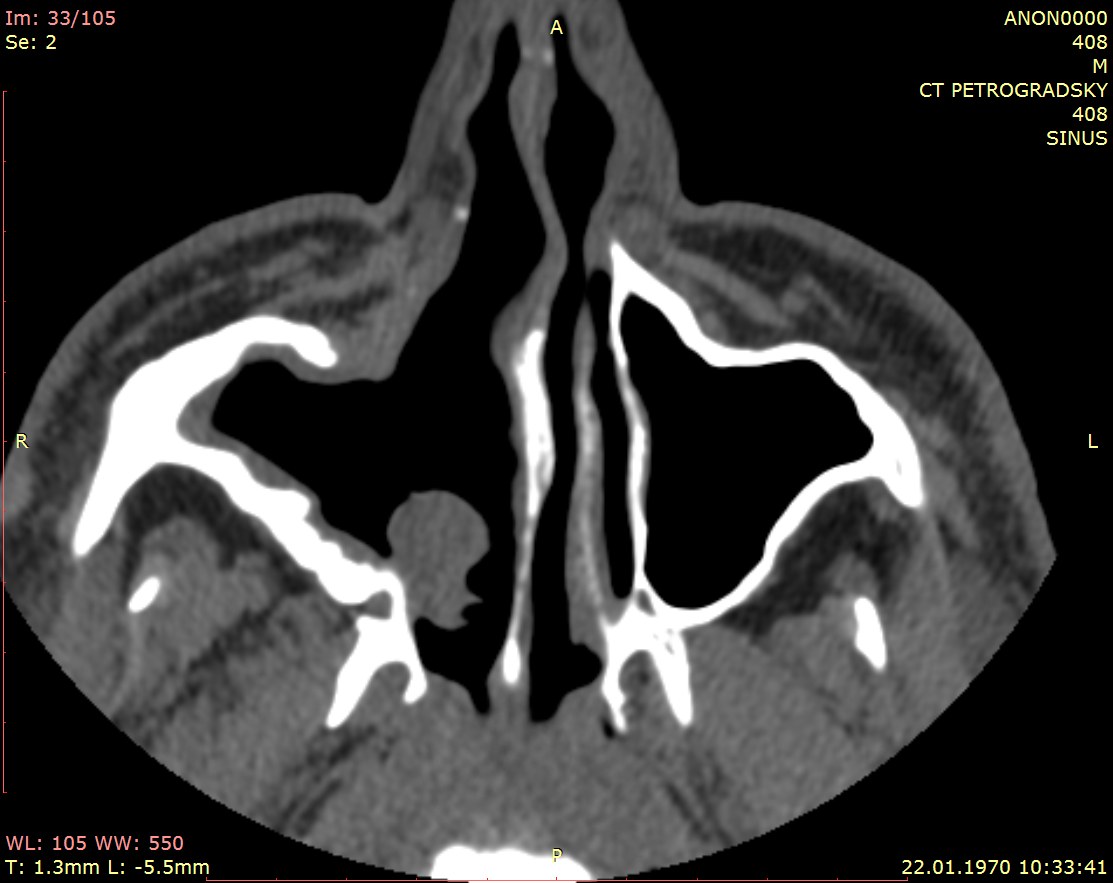

Инвертированная папиллома?

Мужчина 53 лет, много лет назад оперировали на носу, "удаляли полипы".

Очень похоже на инвертированную папиллому - редкое полиповидное доброкачественное новообразование. Интересно, что костные разрастания внутри опухоли (древовидный гиперостоз) указывают на источник ее роста - в нашем случае из латеральной стенки решетчатой пазухи http://www.ajnr.org/content/28/4/618.long

Было бы с 2-х сторон - был бы полипоз, а так как с одной стороны - то очень большая вероятность инвертированной папилломы. Сказать есть или нет зло сможет только гистология. Инвертированные папилломы имеют свойство перерождаються. Но вероятность этого низкая.